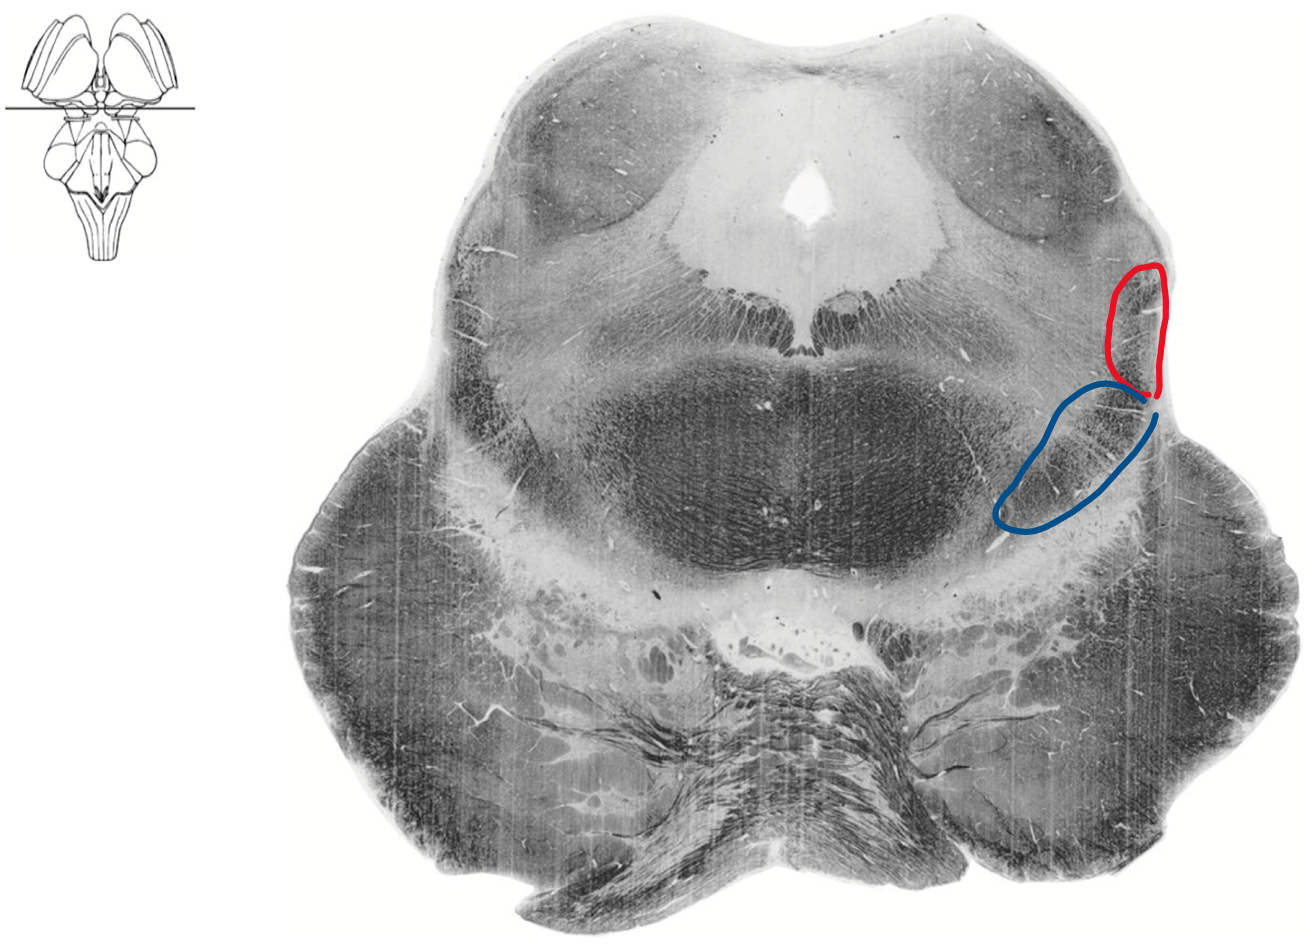

Geisha Caudal midbrain level of inferior colliculus

Boomerang still

Blue medial lemniscus

Red ALS spinothalamic tract

Rostral midbrain level of superior colliculus

Red ALS spinothalamic

Blue Medial lemniscus (DCML)